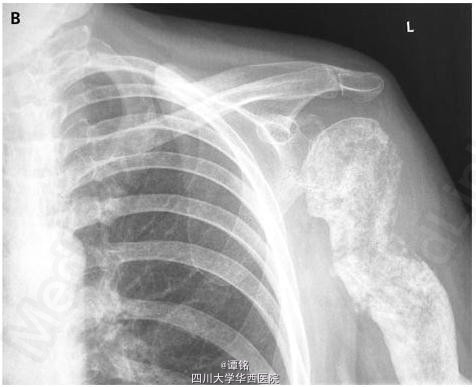

治疗一年来,患者临床症状缓解,左肩功能好转,影像学复查发现左侧肱骨存在骨重建。然而,接下来的四个月,癌转移进展,患者死亡。 DOI: 10.1056/NEJMicm065383